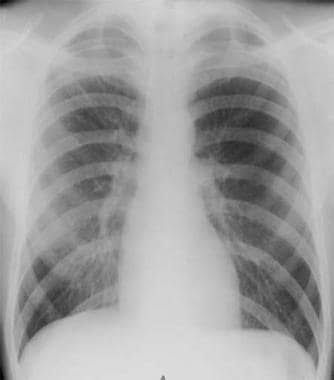

A pneumothorax can be caused by: Chest injury. Any blunt or penetrating injury to your chest can cause lung collapse. Some injuries may happen during physical assaults or car crashes, while others may inadvertently occur during medical procedures that involve the insertion of a needle into the chest. Lung disease. Damaged lung tissue is more likely to collapse. Lung damage can be caused by many types of underlying diseases, such as chronic obstructive pulmonary disease (COPD), cystic fibrosis, lung cancer or pneumonia. Cystic lung diseases, such as lymphangioleiomyomatosis and Birt-Hogg-Dube syndrome, cause round, thin-walled air sacs in the lung tissue that can rupture, resulting in pneumothorax. Ruptured air blisters. Small air blisters (blebs) can develop on the top of the lungs. These air blisters sometimes burst — allowing air to leak into the space that surrounds the lungs. Mechanical ventilation. A severe type of pneumothorax can occur in people who need mechanical assistance to breathe. The ventilator can create an imbalance of air pressure within the chest. The lung may collapse completely.